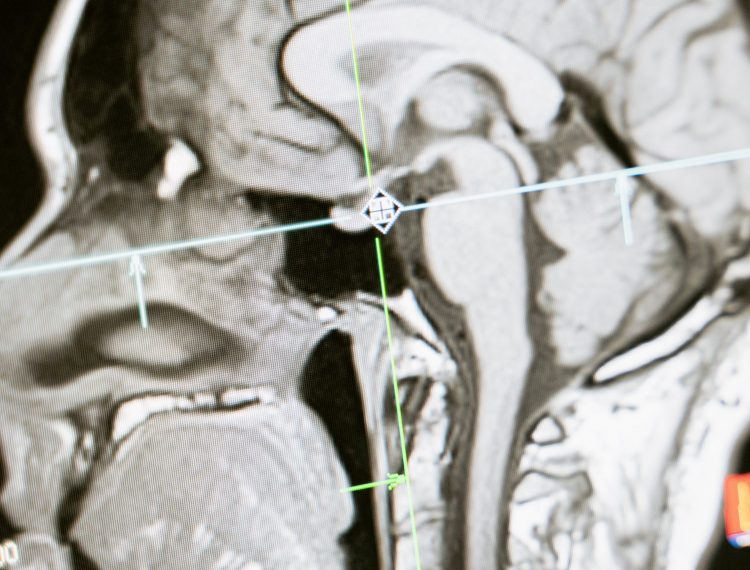

Wenn sich das Gehirn anfühlt, als würde ihm langsam die Luft ausgehen, denkt man fast automatisch an zu wenig Sauerstoff oder zu wenig Durchblutung. Bei CCI liegt das Problem jedoch oft an einer ganz anderen Stelle: Nicht der arterielle Zufluss ist das Problem, sondern der venöse Abfluss.… Weiterlesen